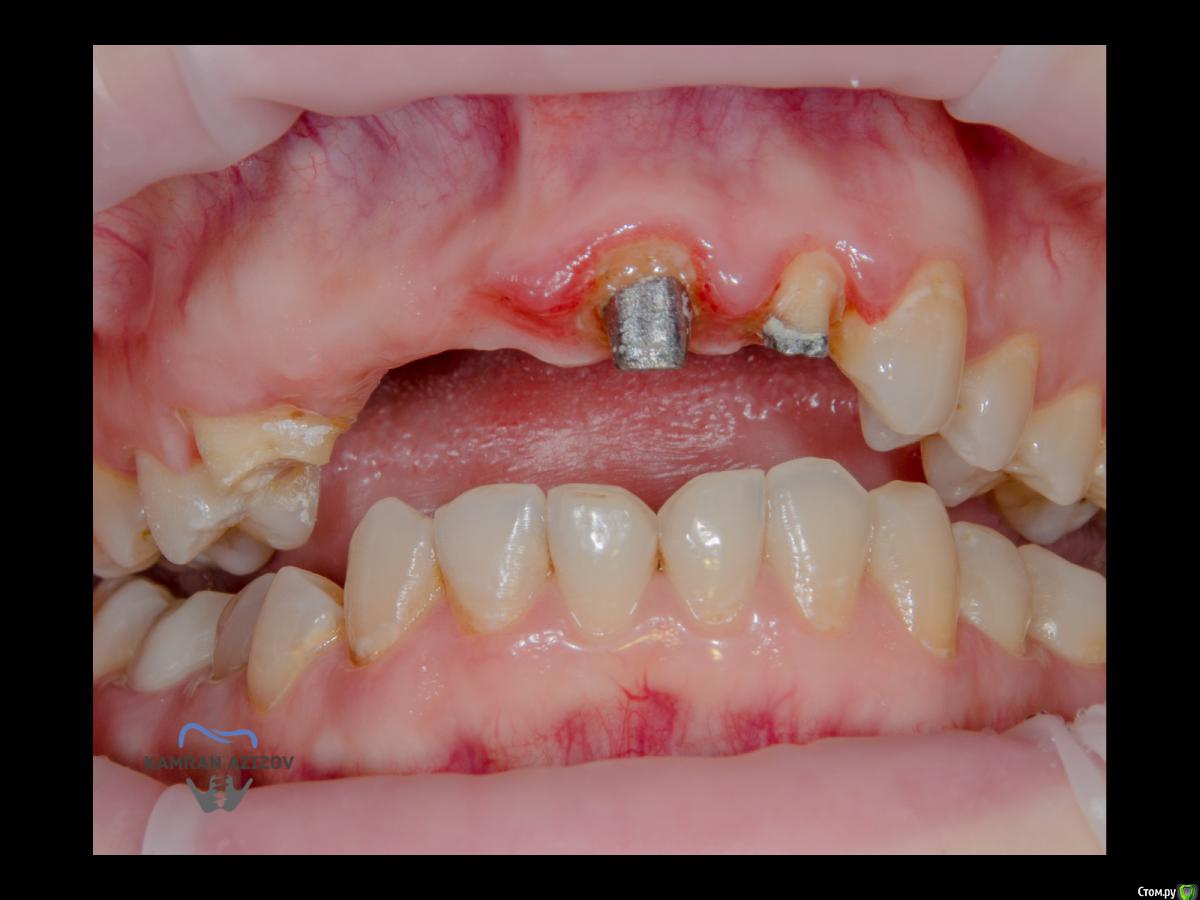

kamranchick Опубликовано 6 апреля, 2019 Поделиться Опубликовано 6 апреля, 2019 (изменено) Хай Гайсдавно ничего не комментировал и не выкладывал, что то настроения не было, да и муза не посещалаСитуация следующаяпришла пациентка, жалобы на неприятный запах из рта, сначала не понял что за хрень, ну как распилил мост понял че к чему... халтура.Ну и по кейсуУдаление клыка и 2ки, через 2 месяца навигация, имплантация + Шашлыки по карлоссу, смена формиков, временное протезирование. только мягкие ткани, Изменено 6 апреля, 2019 пользователем kamranchick 7 1 Ссылка на комментарий

АнтонТЛТ Опубликовано 6 апреля, 2019 Поделиться Опубликовано 6 апреля, 2019 Чё то двойку слишком небно запилил 2 Ссылка на комментарий

kamranchick Опубликовано 6 апреля, 2019 Автор Поделиться Опубликовано 6 апреля, 2019 Ориентировались тут в основном по кости... Ссылка на комментарий